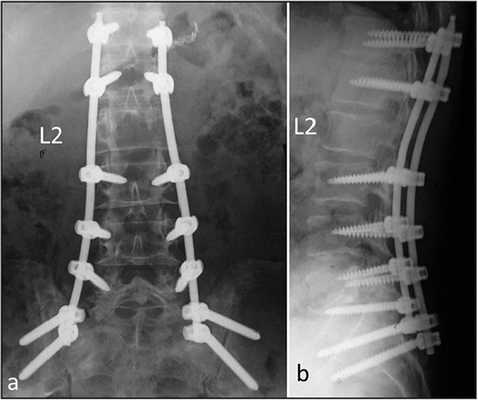

Стабилизация поясничного отдела.

Показаниями к вживлению ригидных конструкций транспедикулярной фиксации, в том числе и Krypton®, служат практически все случаи позвоночной нестабильности:

- выраженный листез позвонков;

- травмы позвоночника (вывихи, переломы и пр.);

- спинальные новообразования;

- дегенеративные патологии, сопровождающиеся неврологическим дефицитом, например, межпозвоночные поясничные грыжи; и кифоз;

- несостоявшийся артродез;

- последствия неудачно выполненных вмешательств и др.

Коррекция кифоза грудного отдела.